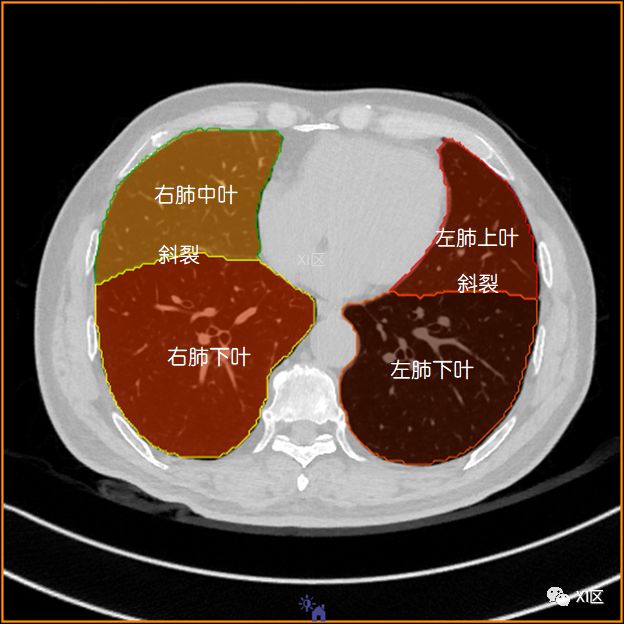

肺的分叶

左肺借斜裂成上、下两叶;右肺借斜裂和水平裂成上、中和下叶三叶。

横断位